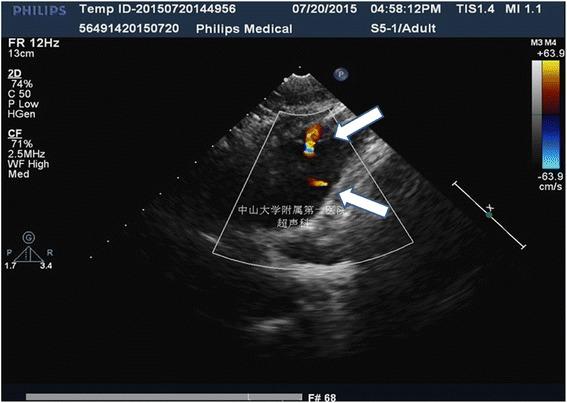

Cardiac arrest is a lethal complication of Nuss repair of pectus excavatum which is strongly related to heart or big vessels injury. A rare case developed cardiac arrest without direct cardiac injury during Nuss procedure is presented in this article.

In July 2015, a previously healthy 18-year-old man undergoing Nuss repair for pectus excavatum developed cardiac arrest while the Nuss bar was being inserted into the chest. After successful resuscitation and exclusion of direct cardiac injury, the Nuss procedure was continued. The patient suffered a second cardiac arrest during rotation of the Nuss bar. This time, the patient had poor initial response to resuscitation and defibrillation until the retrosternal bar was removed. He ultimately recovered well from the episodes of cardiac arrest, but was unable to receive surgical correction of his pectus excavatum deformity.

心脏骤停是漏斗胸Nuss修复术的一种致命并发症,与心脏或大血管损伤密切相关。本文报告1例在Nuss手术期间未发生直接心脏损伤却出现心脏骤停的罕见病例。

2015年7月,一名既往健康的18岁男性在接受漏斗胸Nuss修复术时,在将Nuss钢板插入胸部过程中发生心脏骤停。成功复苏并排除直接心脏损伤后,继续进行Nuss手术。在旋转Nuss钢板时,患者再次发生心脏骤停。此次,患者在复苏和除颤初期反应不佳,直到胸骨后钢板被取出。他最终从心脏骤停发作中恢复良好,但未能接受漏斗胸畸形的手术矫正。